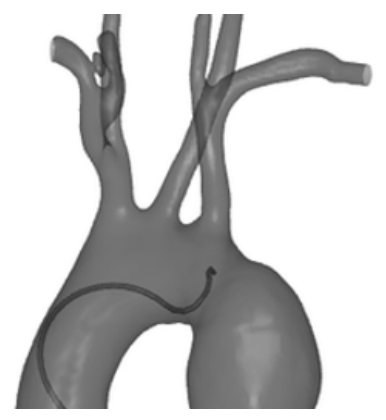

Simulation Data. Apart from X-ray images collected from our real robot, we also collect an EISimulation dataset from the CathSim simulator [2] for simulated X-ray images. We manually label both data from the robot and CathSim simulator to use them in downstream tasks. We note that the datasets used to train the foundation model are not being used in downstream endovascular understanding tasks.